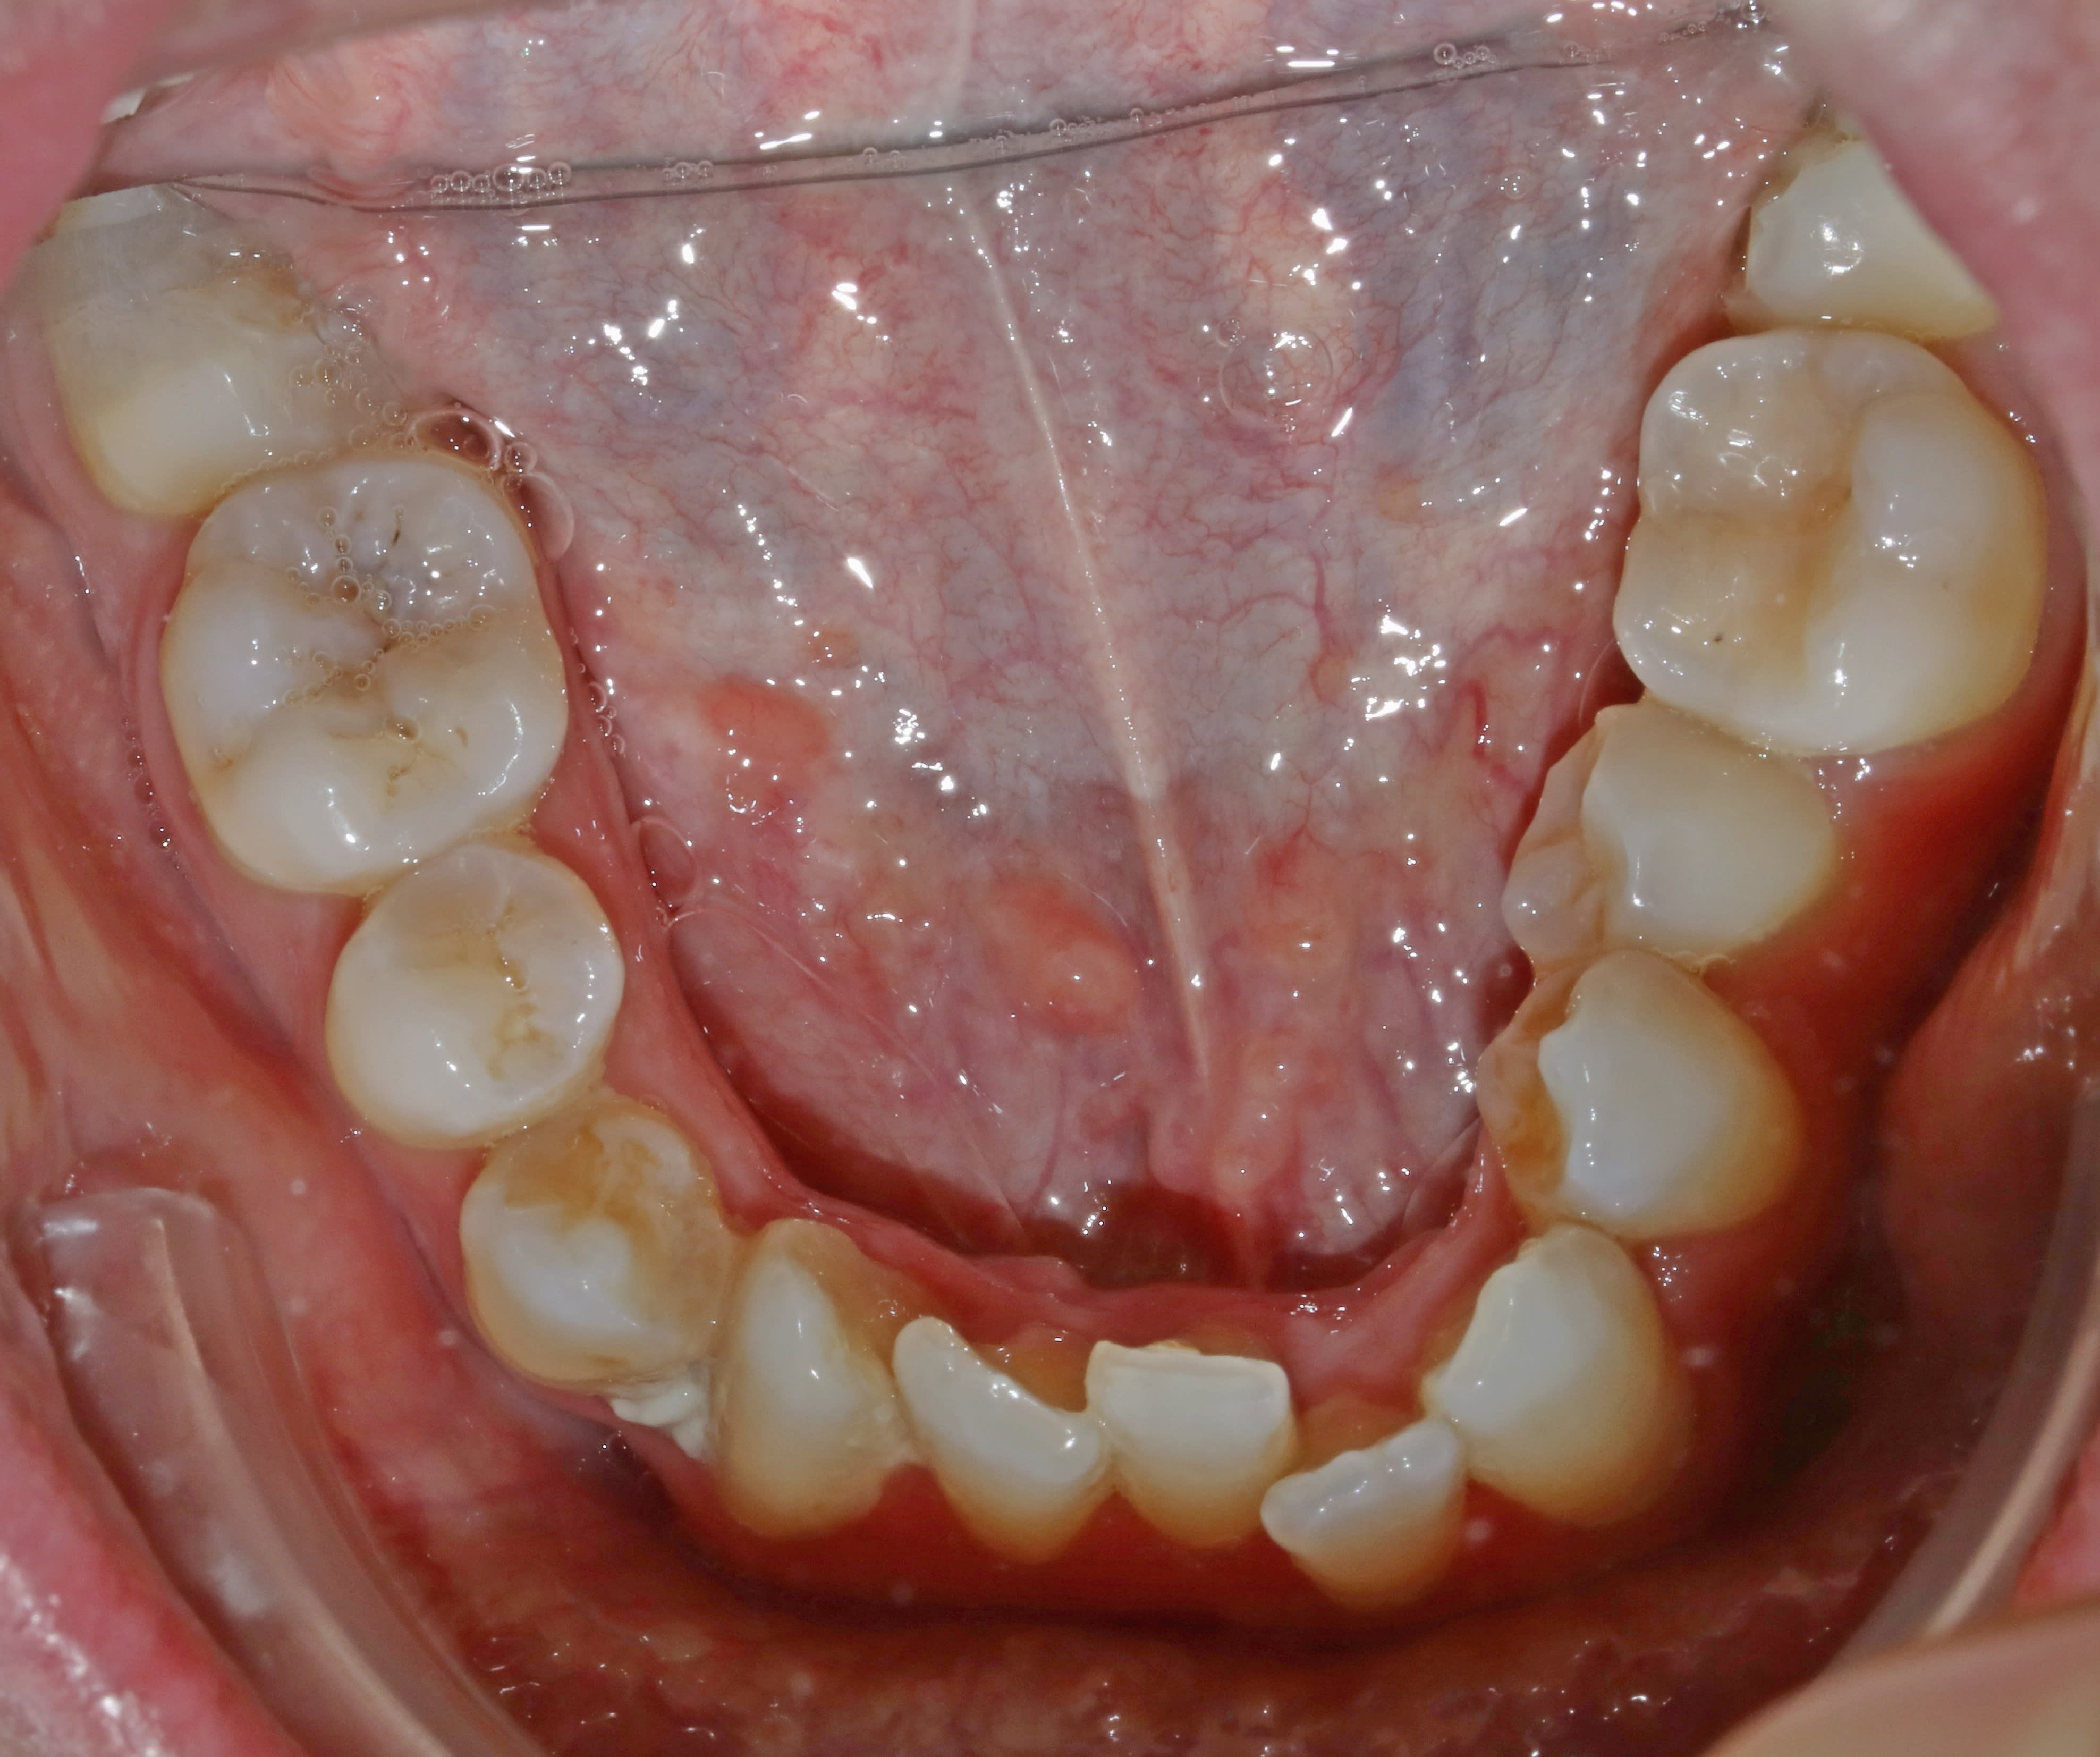

36 ans ...un oublié de l'ortho ...

Arcade md yl4v9v - Eugenol

Arcade mx upxl37 - Eugenol

Droite njf4pn - Eugenol

Face pyrsyz - Eugenol

Gauche snbsdh - Eugenol

sympa, mais au moins il n'a pas 4 CCM soudées en inversé par moitié...